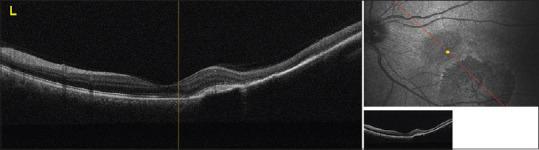

We reported a case of congenital hypertrophy of the retinal pigment epithelium (CHRPE) complicated by choroidal neovascular membrane (CNVM). A 41-year-old woman presented to our clinic with visual loss in the left eye. She was diagnosed as CHRPE complicated by a CNVM. The patient was treated with 2 consecutive monthly intravitreal aflibercept (IVA) injections. The best-corrected visual acuity (BCVA) improved and stabilized at 6/6. Subretinal fluid depending on CNVM resolved completely. CHRPE complicated by CNVM in the macular area is a rare condition and these cases can be treated with IVA therapy.

我们报告了一例先天性视网膜色素上皮肥大(CHRPE)合并脉络膜新生血管膜(CNVM)的病例。一名41岁女性因左眼视力丧失前来我院就诊。她被诊断为CHRPE合并CNVM。该患者接受了连续两个月每月一次的玻璃体内注射阿柏西普(IVA)治疗。最佳矫正视力(BCVA)提高并稳定在6/6。依赖于CNVM的视网膜下液完全消退。黄斑区CHRPE合并CNVM是一种罕见情况,这些病例可采用IVA疗法治疗。